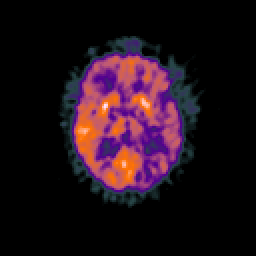

Glioma overlay -- Slice #59

[Home][Help][Clinical] Slice 59